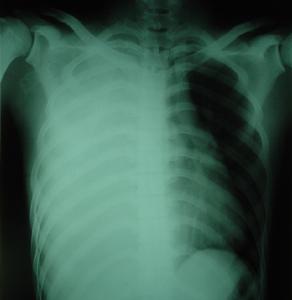

血胸的臨床表現隨出血量、出血速度、胸內器官創傷情況和傷員體質而差異。肋骨骨折並發少量血胸,一般失血量較少,臨床上不呈現明顯症狀。出血量多,超過1000ml,且出血速度快者,則呈現面色蒼白、脈搏快而弱、呼吸急促、血壓下降等低血容量休克症狀,以及胸膜腔大量積血壓迫肺和縱隔引致呼吸困難和缺氧等。小量血胸常無異常體徵。大量血胸則可呈現氣管、心臟向健側移位,傷側肋間隙飽滿,叩診呈實音。血、氣胸病例則上胸部呈鼓音,下胸部實音。呼吸音減弱或消失。由於肺撕裂而引起的血胸傷員常有咯血。積留在肋膈竇的小量血胸,胸部X線檢查可能不易被發現,或見到肋膈角消失。血胸量較多者,則顯現傷側胸部密度增大。在側臥位胸片上顯示比較清楚。大量血胸則顯示大片濃密的積液陰影和縱隔移位徵象。血、氣胸病例則顯示液平面。胸膜腔穿刺抽得血液則可確定診斷。血胸病人經穿刺抽血,胸膜腔積液減少後,可又增多。胸膜腔內血液凝固,穿刺未能抽出血液或僅能抽出少量血液,但休克症狀加重或X線檢查胸膜腔積液量增多;胸膜腔引流後每小時引流量超過200ml並持續2小時以上者,都提示有進行性出血,需及時處理。

血胸演變形成纖維胸,如範圍較大者可出現病側胸廓塌陷,呼吸運動減弱,氣管、縱隔向病側移位,肺通氣量減少。X線檢查顯示纖維板造成的濃密陰影。